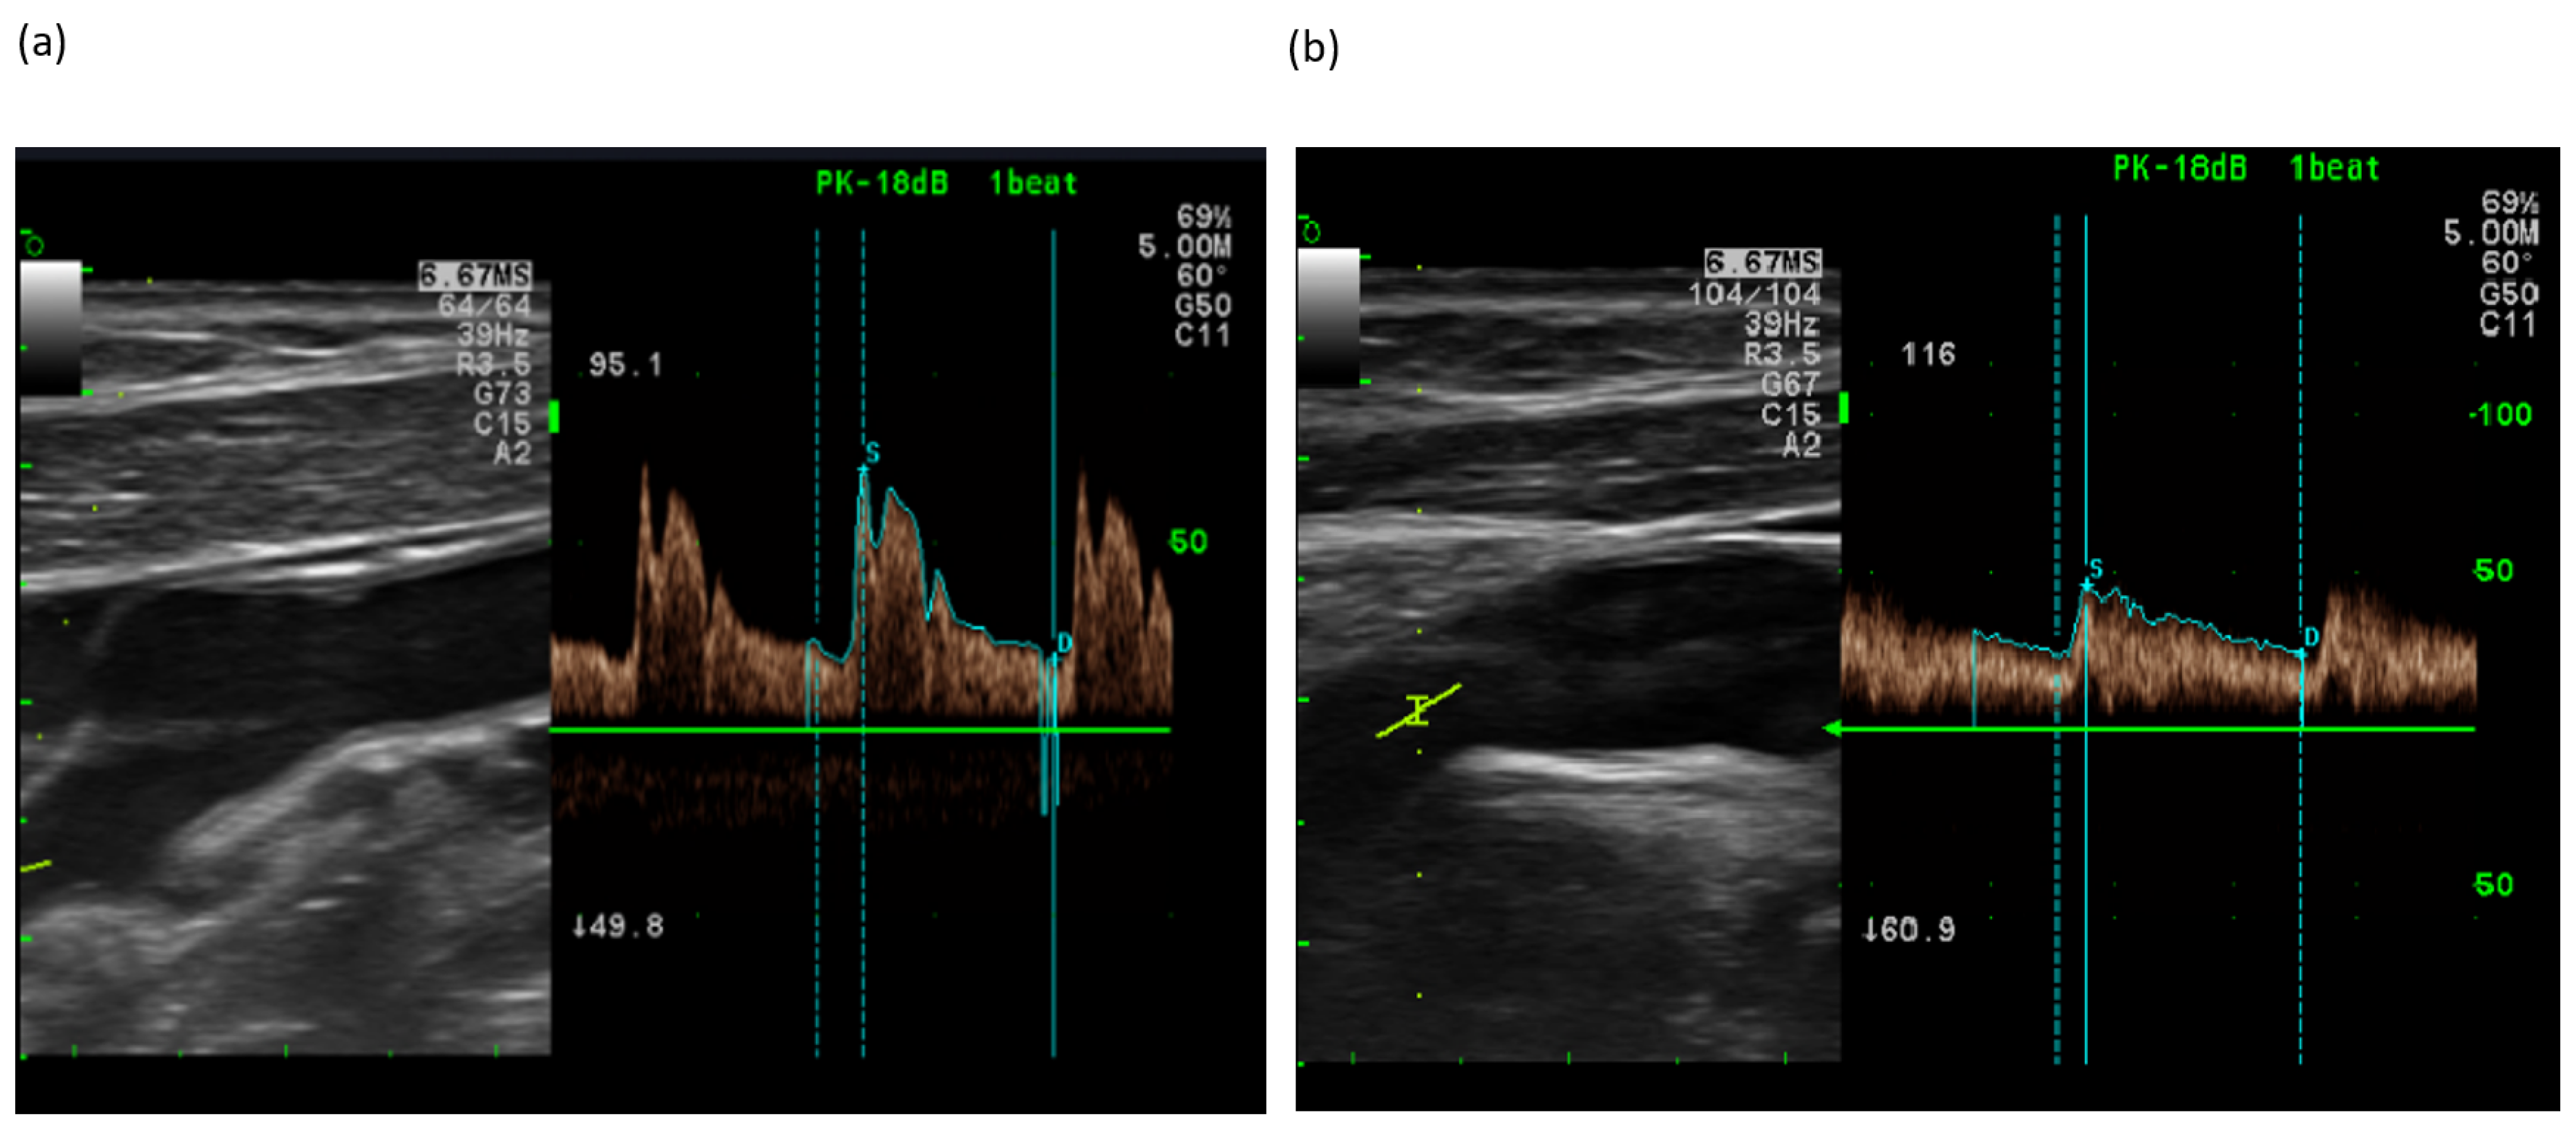

2.5.2. Doppler Ultrasonography (CA and BP)

3.2. Changes in BP and CA Velocity